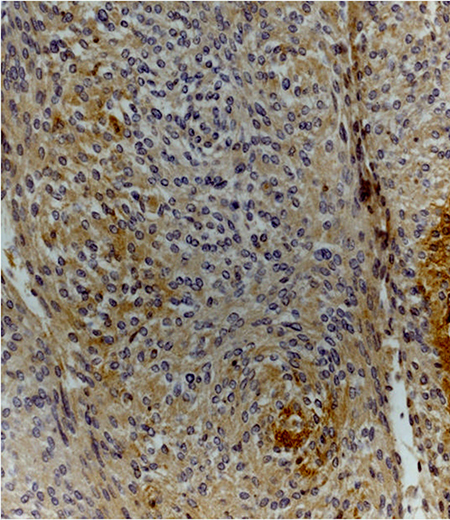

Immunohistochemistry analysis showed that Dkk-3 and claudin-5 were expressed in all cases, though with different ID score and sub-cellular distribution. In particular, among grade I meningiomas, Dkk-3 had ID score 1 in 4 cases, ID score 2 in 7 cases, ID score 4 in 2 cases and ID score 8 in 2 cases (Figure 1). On the other hand, in grade II meningiomas Dkk-3 ID score was 1 in 11 cases, 2 in 3 cases and 3 in 1 case (Figure 1). In addition, while all grade I meningiomas had both cytoplasmic and nuclear staining for Dkk-3 (Figure 2), grade II tumors had only cytoplasmic staining for this protein (Figure 3). Dkk-3 immuno-expression was also found in the nuclei of the endothelial cells of some vessels in all meningiomas.

Figure 2: Transitional (grade I) meningioma showing moderately intense cytoplasmic and nuclear staining for Dkk3 (Dkk3 stain; original magnification, x200).

Figure 3: Atypical meningioma (grade II) with weak cytoplasmic staining for Dkk3 (Dkk3 stain; original magnification, x200).